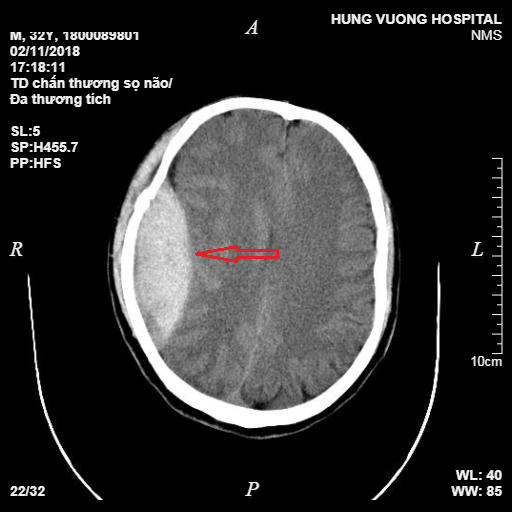

Bệnh nhân được thực hiện các cận lâm sàng cần thiết, kết quả chụp CT đa dãy sọ não cho thấy hình ảnh tụ máu ngoài màng cứng vùng thái dương - đỉnh phải, 1/3 bán cầu, chèn ép gây thoát vị thùy thái dương phải, vỡ xương thái dương và xương đỉnh phải.